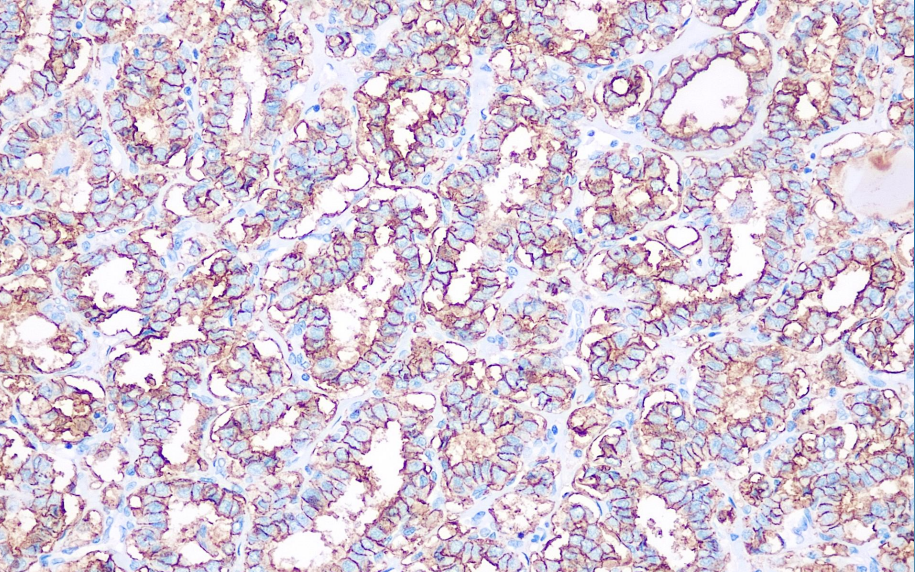

Cellular localization: cytoplasm/membrane

Positive control: papillary thyroid carcinoma

This antibody can recognize 17/19 epithelial mesothelioma, and its staining pattern presents a special "thick film" pattern. It is mainly used in the research of malignant mesothelioma.

MC antibody reagents can specifically bind to MC antigens. Immunohistochemical kits containing MC antibody reagents are suitable for the precise diagnosis of malignant mesothelioma.